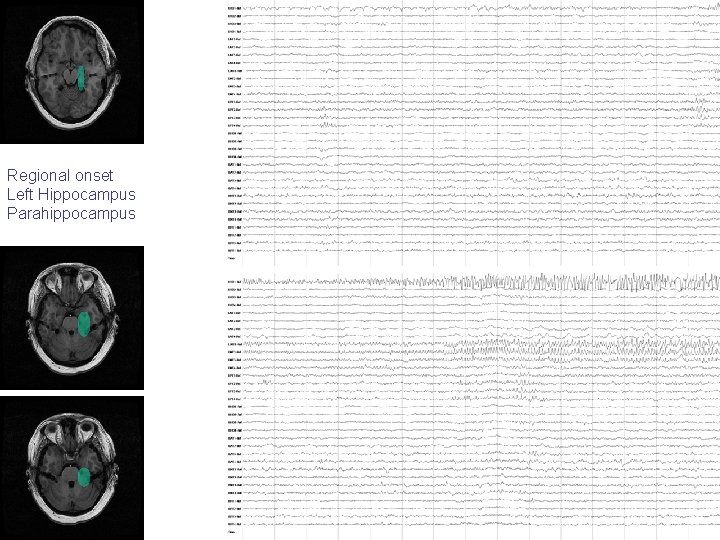

Focal onset Left Hippocampus

Regional onset Left Hippocampus Parahippocampus